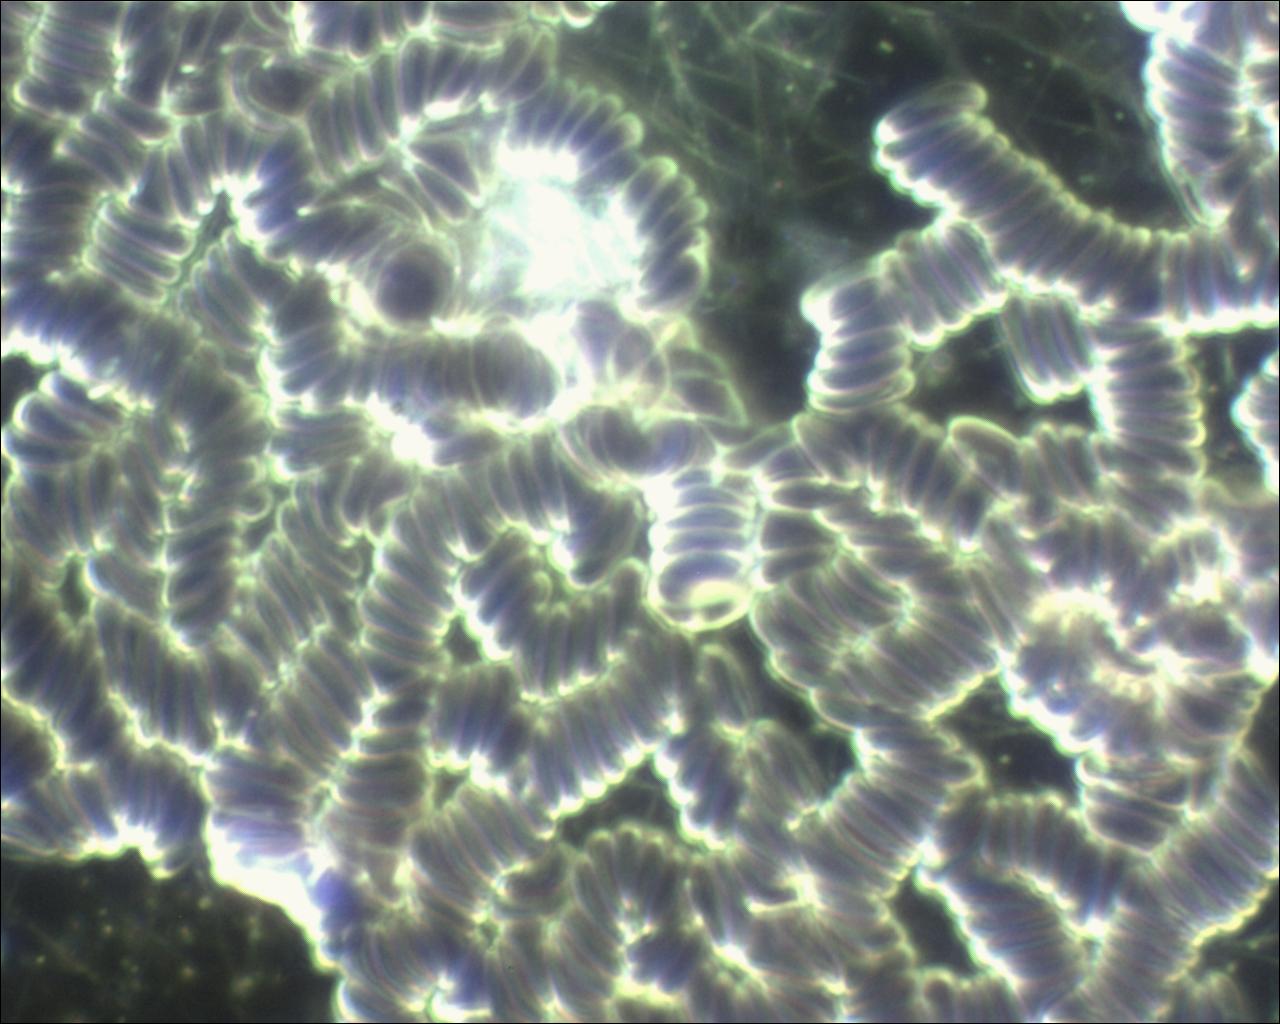

Im Folgenden habe ich einige Aufnahmen mit Objekten und „Zuständen“, die durch Therapeuten abgeklärt werden können:

In dieser Aufnahme (ca. 20 Minuten nach Abnahme), sehen Sie, dass die roten Blutkörperchen nicht mehr alle ganz „rund“ sind. Zudem sehen wir zunehmend mehr kleine „Striche“ / Stäbchen die sich bilden.

Hier wird es schon schwieriger. Die roten Blutkörperchen liegen jetzt nicht mehr nebeneinander getrennt (siehe oben), sondern liegen jetzt eher senkrecht zusammen wie bei einer Geldrolle. Dieses Phänomen wird generell als „Übersäuerung“ oder „Darmbelastung“ gewertet, aber ich rate zur Vorsicht mit vorschnellen Diagnosen. Es kann auch einfach ein Blutentnahme-Fehler sein.

Das Problem der Dunkelfeldmikroskopie ist, wie diese Veränderungen im Blut (die bei der mehrstündigen Betrachtung auftreten) zu bewerten sind.

Die vorhandene Literatur stützt sich auf wenige Anwender, die verschiedene Phänomene beschreiben und teilweise zu unterschiedlichen Aussagen kommen.